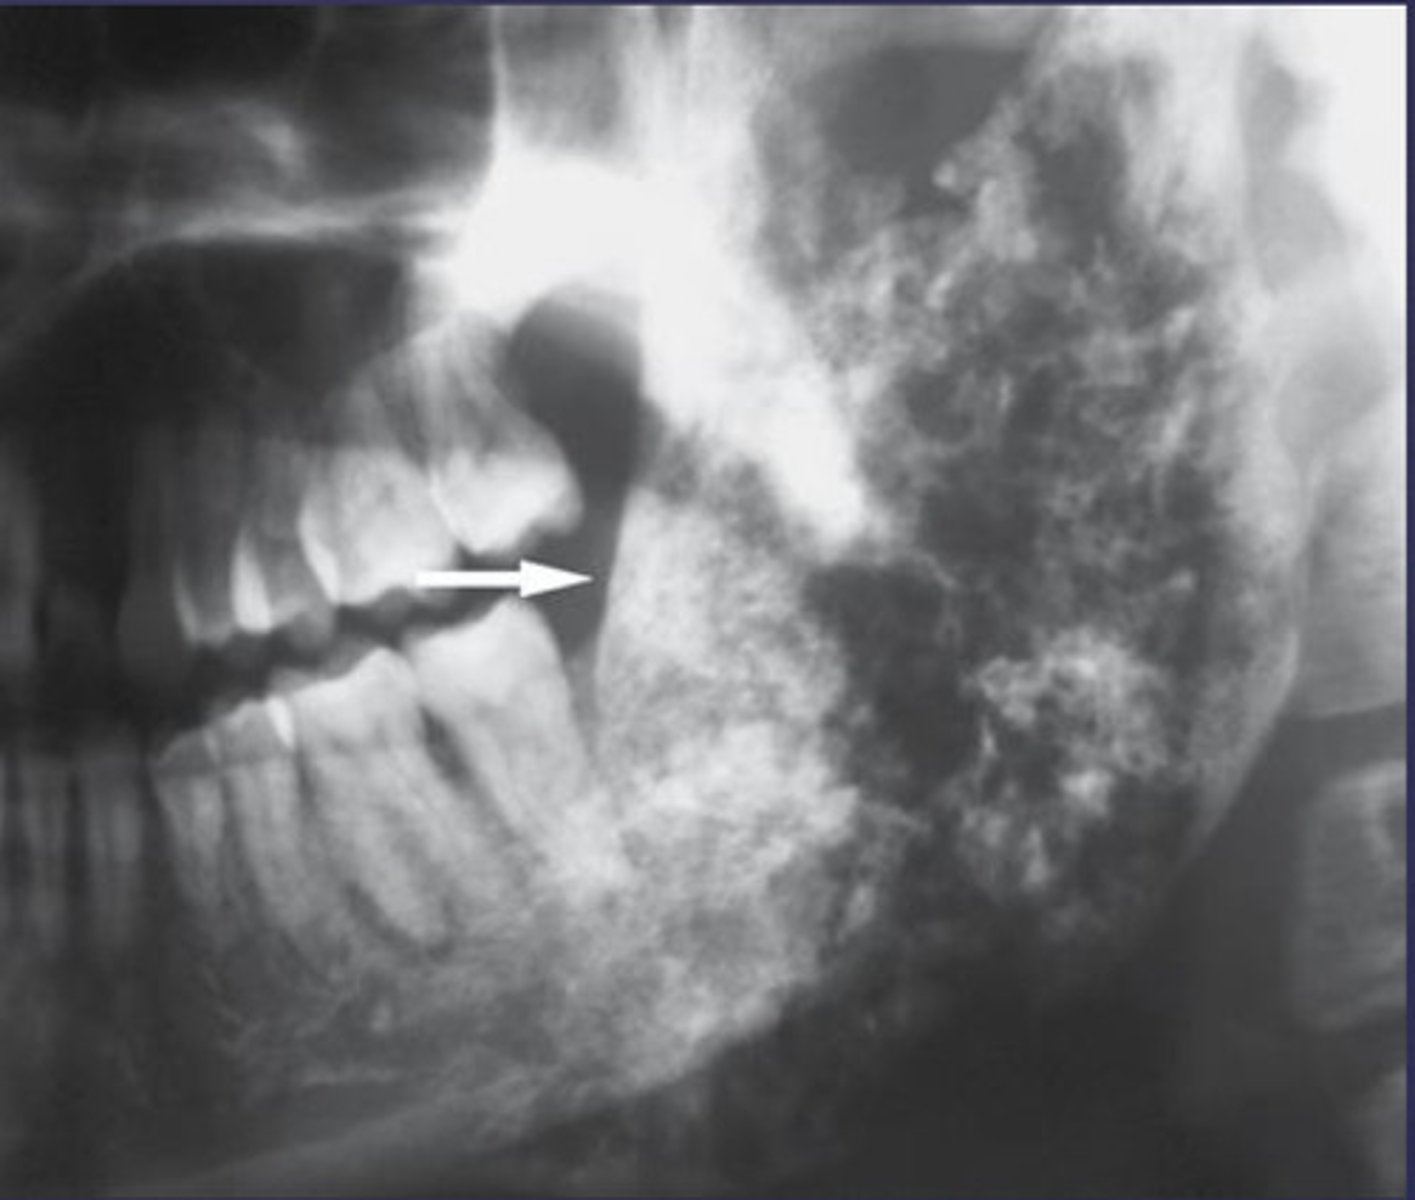

how would you describe this lesion? (not the giant cavity btw)

A. defined, corticated, periapical radiolucency causing loss of lamina dura and PDL space on #6-7

B. defined, non-corticated, periapical radiolucency causing loss of lamina dura and PDL space on #6-7

C. ill-defined, circular radiolucency located above tooth #7

D. well-defined, corticated, radiopacity

- Also note epicenter located above apex # 7 which has large dental caries.

What category would this lesion be part of?

Inflammation/benign

all of the following could be a differential diagnosis for the following lesion EXCEPT?

A. radicular cyst

B. Periapical granuloma

C. apical rarefying osteitis

D. renal osteodystrophy

what category would this lesion be classified into?

inflammatory/benign cystic